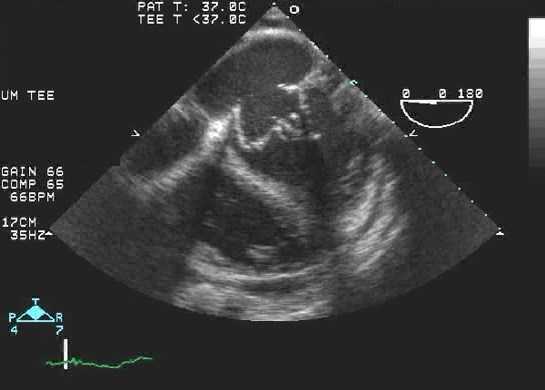

При выявлении препятствий для прохождения ультразвука (ожирение, присутствие искусственных клапанов) и при тяжелых заболеваниях сердца используют чрезпищеводную ЭхоКГ, во время которой датчик вводят через пищевод вплотную к левому предсердию. В течение 4—6 часов до процедуры пациент должен воздержаться от курения, не употреблять воду и пищу. Также следует извлечь съемные зубные протезы, если таковые имеются.

ЭхоКГ не позволяет отличить доброкачественные опухоли от злокачественных. 2-D эхокардиография показывает опухоли как эхогенные образования в полости сердца, прикрепленные к стенке или находящиеся в перикарде. Обычно их размер и мобильность можно хорошо определить. Как и во всех исследованиях при проведении ЭхоКГ, необходимо получить несколько изображений. Иногда в M-режиме можно увидеть опухоль, такую как миксома, нарушающая функцию клапана. Эффекты опухолей (например, обструкция клапана, дисфункция ЛЖ из-за инфильтрации, обструкции или перикардиального выпота) также можно увидеть на эхокардиографии.

Миксомы могут быть легко обнаружены с помощью M-режима или 2-D эхокардиографии. Миксома может рассматриваться как образование в полости ЛП и может пролабировать через МК в полость ЛЖ во время диастолы, затрудняя кровоток. Она может быть настолько большой, что заполняет все предсердие. Допплер может показать гемодинамические эффекты данной опухоли.